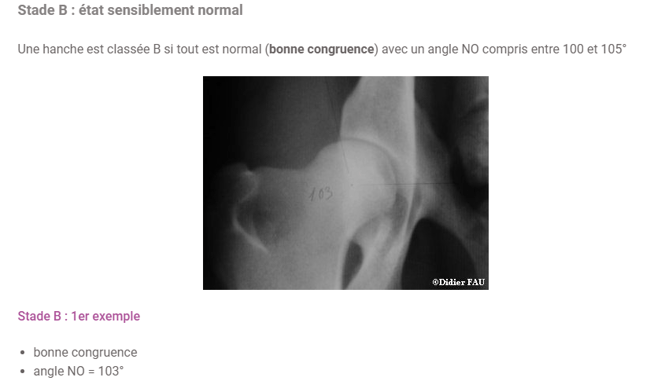

https://www.vetopedia.fr/dysplasie-de-la-hanche-chez-le-chien-stades-radiologiques/

Il y a deux cas pour B, lisez c'est intéressant